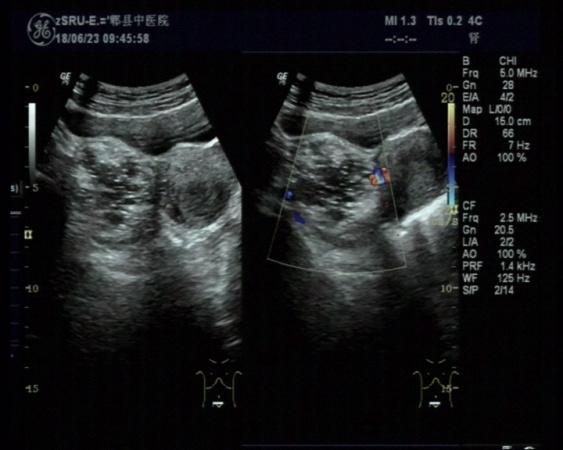

右侧附件区畸胎瘤可能

女,30岁,既往体检无异常,此次超声检查如图所示:右侧附件区探及一杂乱不均回声团,边界清楚,形态规则,CDFI:周边可见少许血流信号。